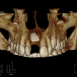

Interdisciplinary Treatment of Patients with Deep Overbite and Parafunctional Activity

Bruxism is defined as parafunctional grinding of teeth and due to the excessive wear of the posterior teeth, patients with long-standing bruxism often have pathological deep overbite. For many decades, treatment of bruxism and deep overbite was focused on reshaping the bite for achieving an occlusion free of deviations. Despite large efforts, the management of bruxism and subsequent deepening overbite was not obtained.